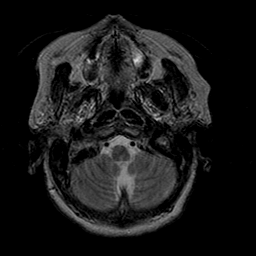

Stroke:T2-weighted MR #1 -- Slice #2

[Home][Help][Clinical] Slice 2